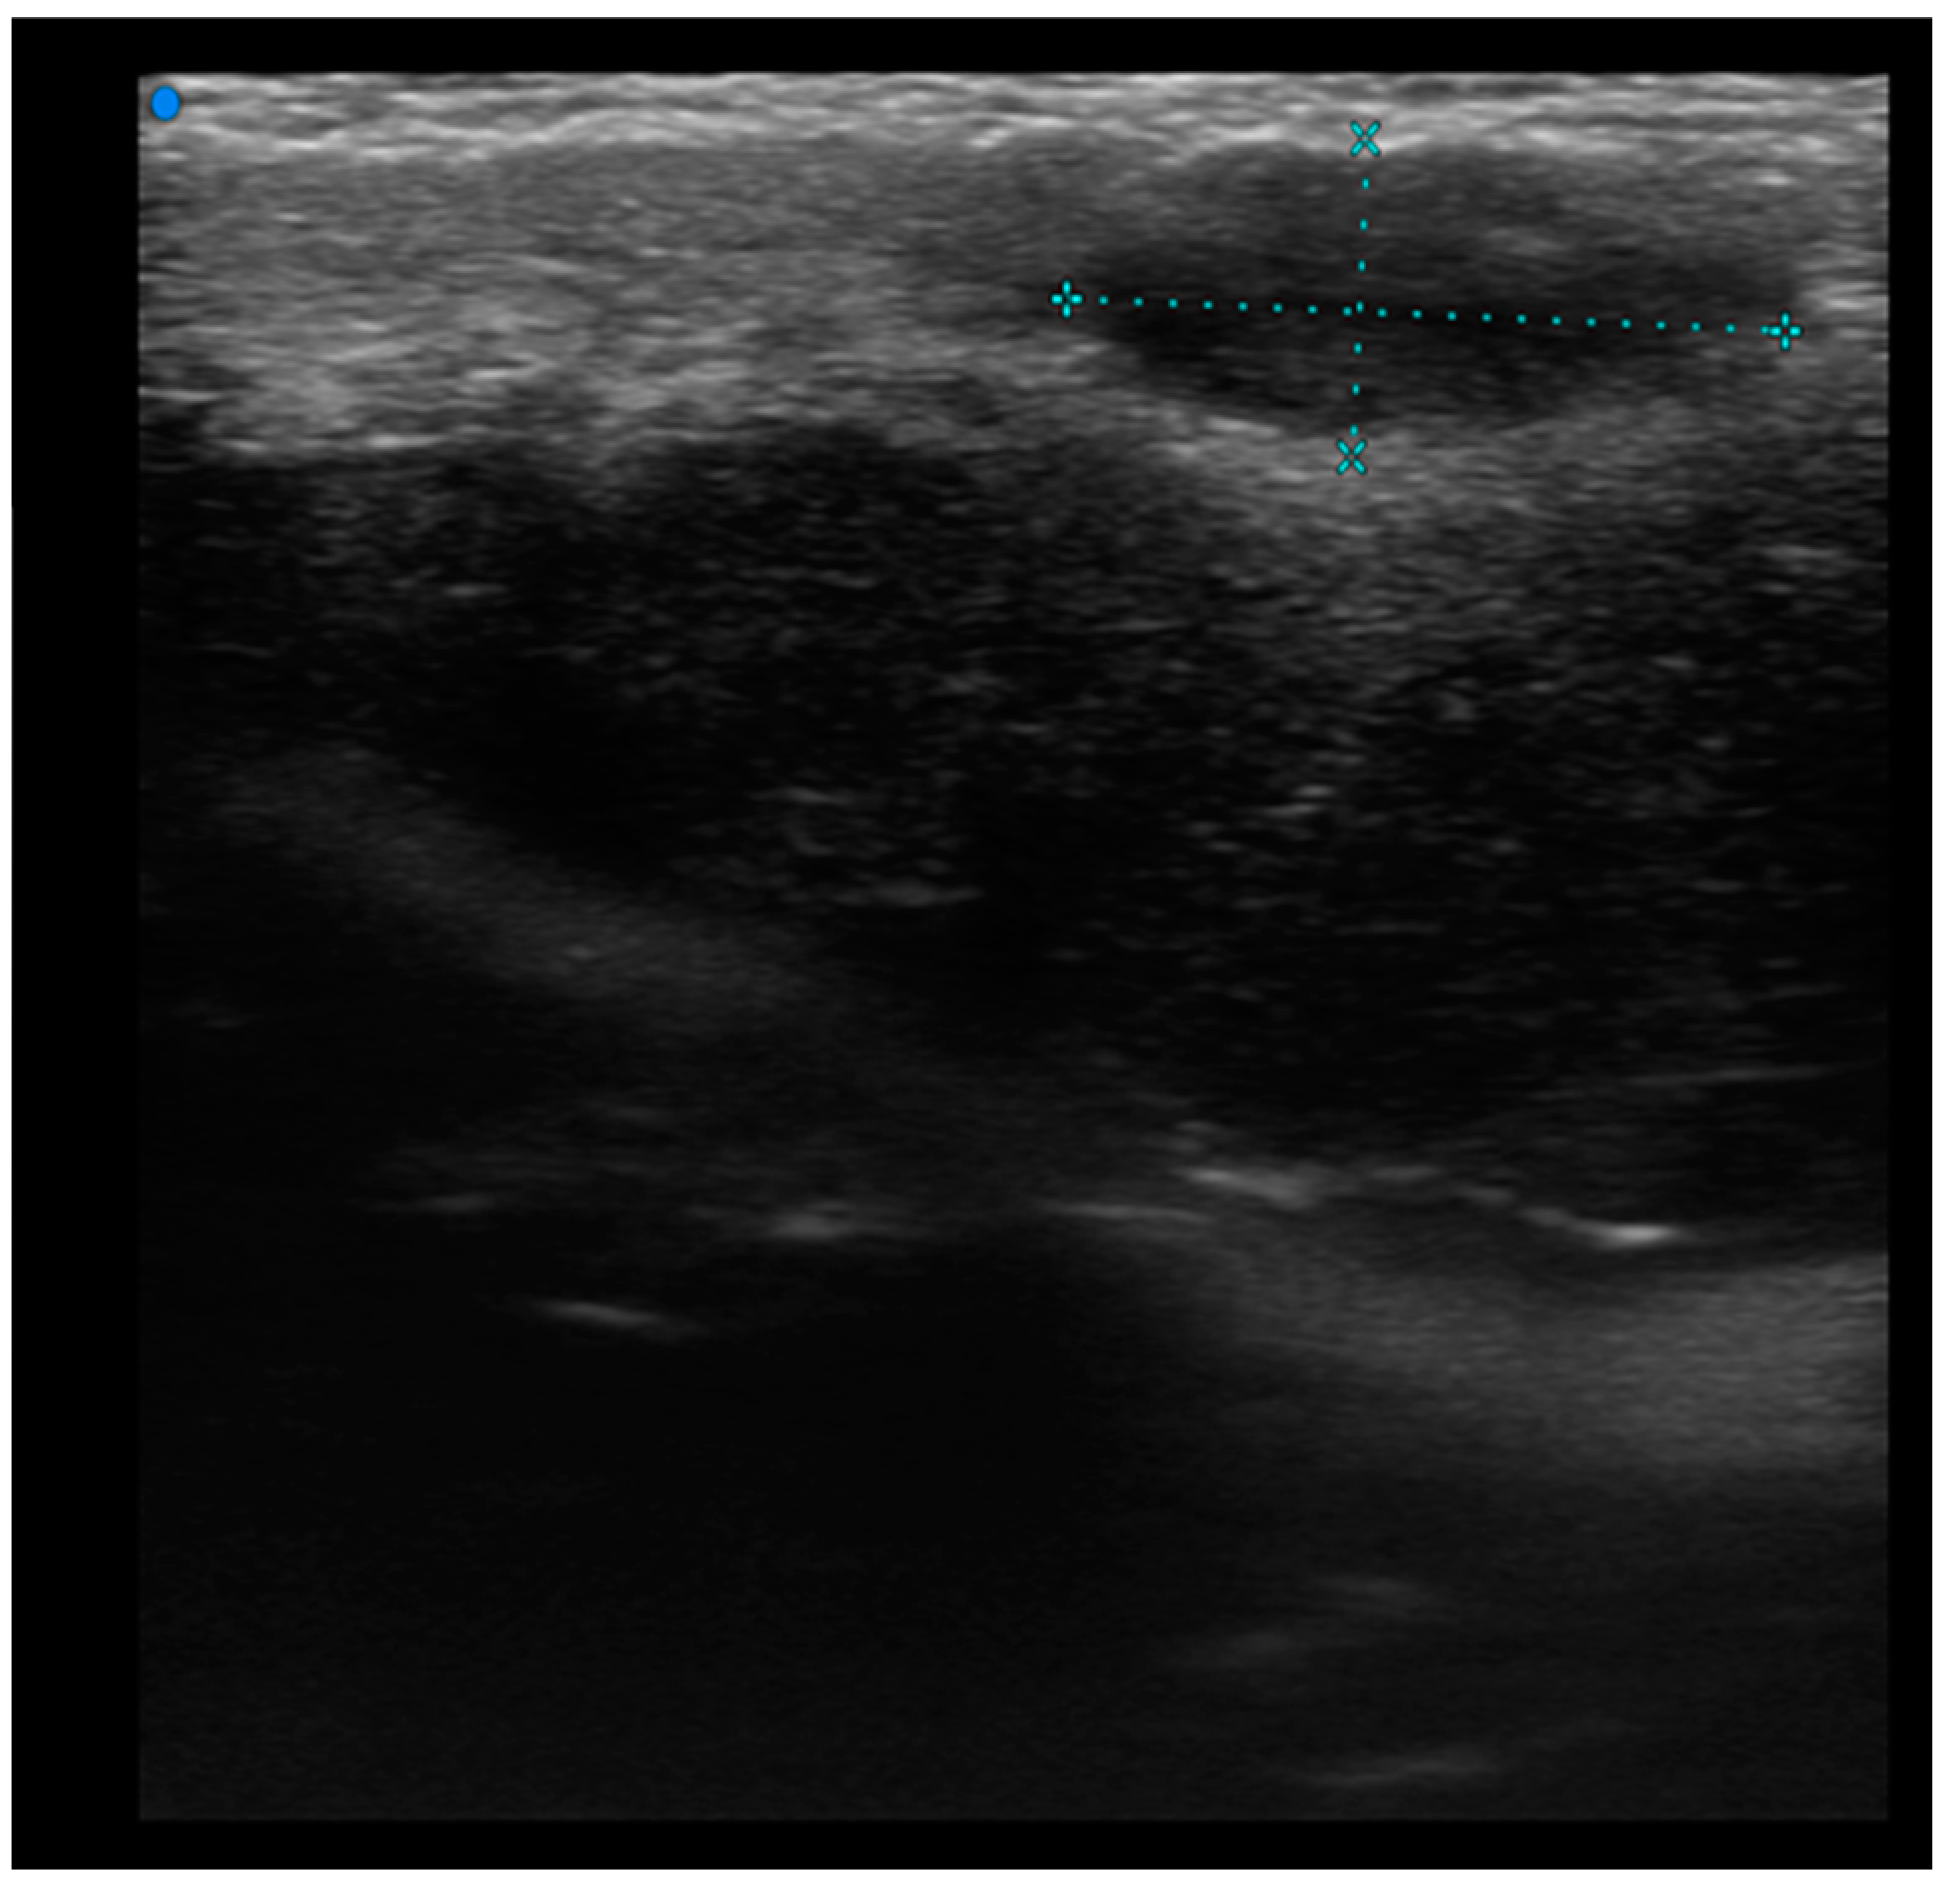

Pseudonodular and nodular lesions were more frequently observed in B-cell lymphomas (70%), while diffusely infiltrative lesions were equally prevalent in both B-cell and T-cell lymphomas (50% each) (Figure 5).

High-Frequency ultrasound (HFUS) revealed dermal thickening in all cases, with no evidence of necrosis, calcification, or posterior acoustic shadowing in any of the lesions. Color Doppler imaging showed that initial focal infiltrative lesions were avascular, whereas nodular, pseudonodular, and diffusely infiltrative lesions were highly vascular. In contrast, nodular or multinodular lesions clustered in the epidermal and subepidermal layers with dermal involvement and clear or irregular margins, with or without peripheral infiltration, were more indicative of T-cell lymphoma. Plaque-like lesions showing iso-hypoechoic characteristics and clear margins, with or without dermal infiltration, were consistent with mycosis fungoides (Figure 6).

Figure 7. Diffuse infiltrative lesion (recurrence of B-cell lymphoma) examination performed with a very high-frequency ultrasound probe at 50 MHz in the region of the right scapula: Iso-hypoechoic lesions with nodular and multilobulated morphology and irregular margins infiltrating the epidermal and subepidermal tissue.